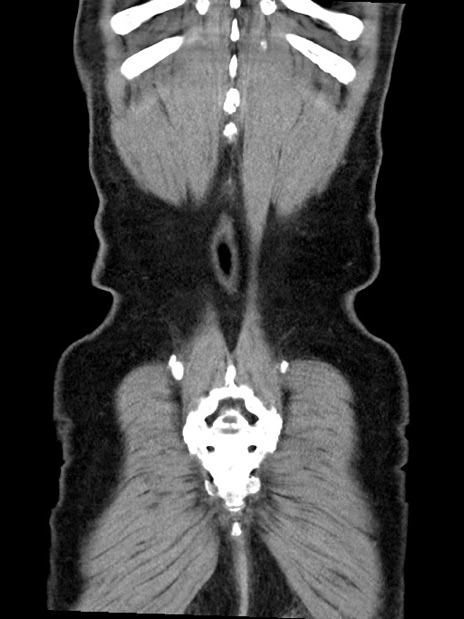

症例35(冠状断像)

【症例】70歳代 男性

【主訴】腹部膨満、嘔吐

【現病歴】昨日より腹部膨満感出現。本日増悪し、仙痛出現。嘔吐あり、受診。

【既往歴】糖尿病、胆摘後

【身体所見】BP 149/80mmHg、HR 74/min、BT 35.9℃、腹部:膨満、軟、圧痛なし。腸雑音減弱あり。上腹部正中切開瘢痕あり。

【データ】WBC 13500、CRP 1.72